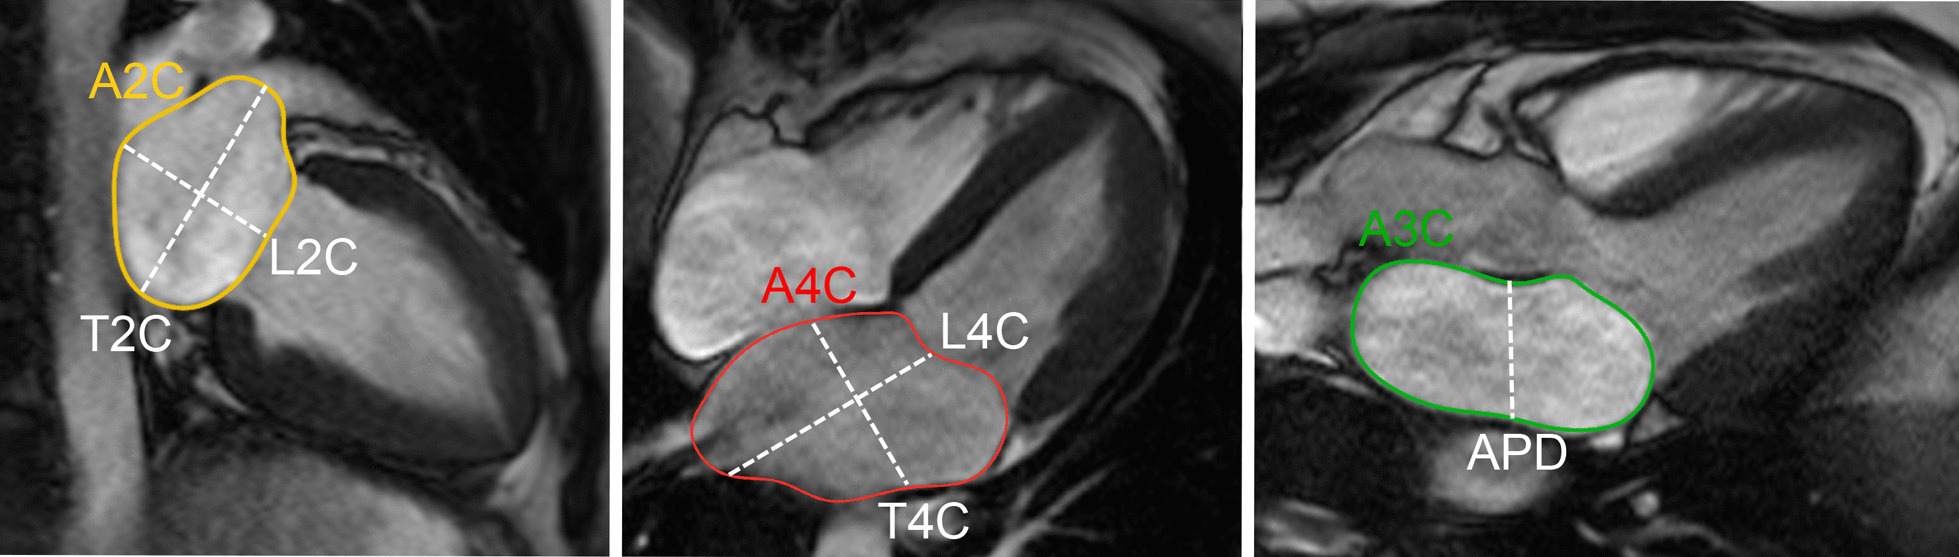

LA longitudinal and transverse diameters and area have been measured on 2, 3, and 4 chamber cine bSSFP images [31, 33, 35] (Fig. 3).

Fig. 3.

Measurement of left atrial area (A2Ch, A4Ch, A3C), longitudinal (L2Ch, L4Ch), transverse (T2Ch, T4Ch) and anteroposterior (APD) diameters on the 2-, 4- and 3-chamber views according to reference [31]